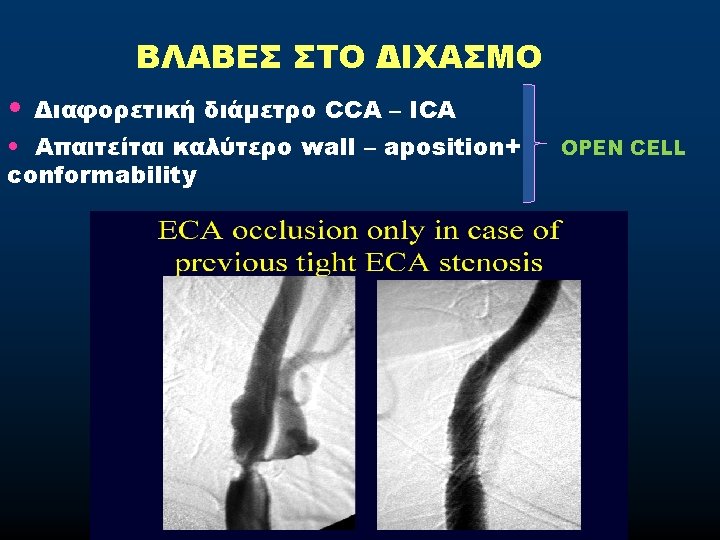

• MISMATCH CCA-ICA